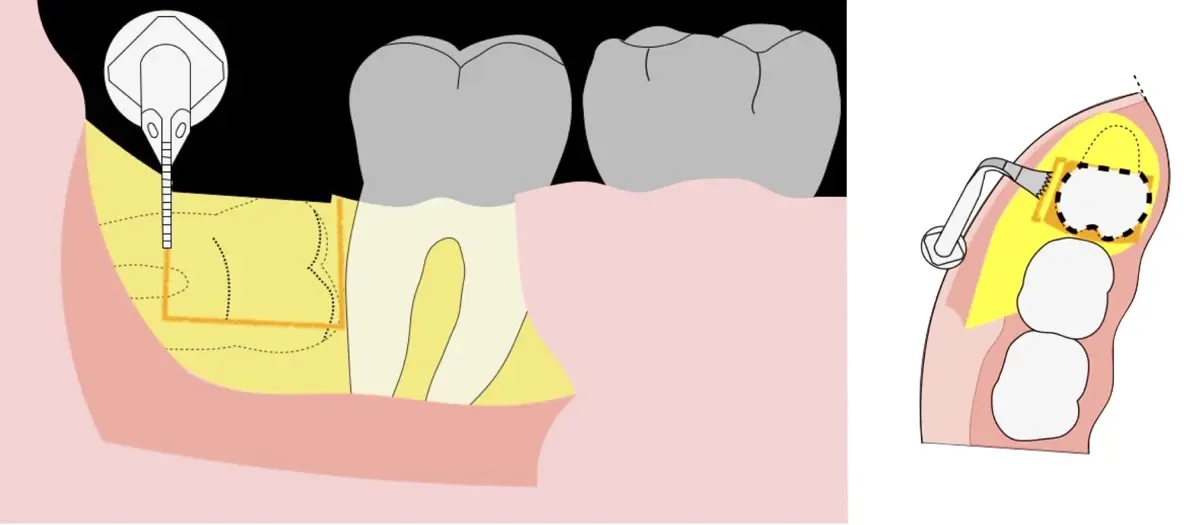

Figura 8. Odontosección mediante fresa de alta rotación y/o inserto de corte de piezoeléctrico. Posteriormente se procede al ensanchamiento del espacio pericoronario con el periótomo de piezoeléctrico para facilitar la avulsión de la pieza dentaria.

Figura 9. Avulsión de la parte coronaria de la tercera molar.

Figura 10. Tracción mesial del remanente dentario utilizando botadores en bandera.